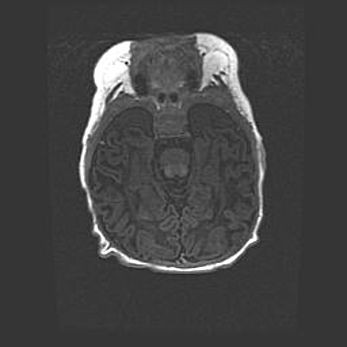

Лейкомаляция с кистозно-глиозной дегенерацией головного мозга.

Возраст: 2 месяца 25 дней

Вес: 6400 г

Окружность головы: 40 см

Срок гестации: 41 неделя

Лейкомаляцию относят к ишемически-гипоксическим повреждениям головного мозга, диагностируемым у новорожденных. При лейкомаляции в головном мозге обнаруживают очаги некроза, возникшие после тяжелой гипоксии и нарушения кровотока. В процессе морфогенеза очаги проходят три стадии: 1) развития некроза, 2) резорбции и 3) формирования глиозного рубца или кисты. Перивентрикулярная лейкомаляция (ПЛ) встречается примерно в 12% случаев среди новорожденных, обычно – у недоношенных детей, причем, частота ее зависит от массы, с которой младенец появился на свет. Наибольшее число малышей страдает лейкомаляцией, если масса при рождении 1500-2500 г.